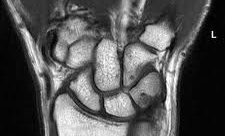

מאת: עופר בן חורין. בדיקת MRI שורש כף היד היא בדיקה אשר מספקת הזדמנות לדמות את שורש כף היד (wrist) ברזולוציה גבוהה ובמנחים שונים. ביצוע בדיקת MRI שורש כף היד יעילה במצבים של לאחר טראומה, נמק העצם (AVN- avascular necrosis; מצב שבו נגרמת הפרעה באספקת דם…לחצו להמשך קריאה